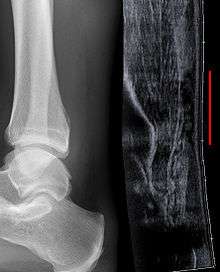

Imaging

Musculoskeletal ultrasonography can be used to determine the tendon thickness, character, and presence of a tear. It works by sending extremely high frequencies of sound through the body. Some of these sounds are reflected back off the spaces between interstitial fluid and soft tissue or bone. These reflected images can be analyzed and computed into an image. These images are captured in real time and can be very helpful in detecting movement of the tendon and visualising possible injuries or tears. This device makes it very easy to spot structural damages to soft tissues, and consistent method of detecting this type of injury. This imaging modality is inexpensive, involves no ionizing radiation and, in the hands of skilled ultrasonographers, may be very reliable.

Radiography can also be used to indirectly identify Achilles tears. Radiography uses X-rays to analyse the point of injury. This is not very effective at identifying injuries to soft tissue. X-rays are created when high energy electrons hit a metal source. X-ray images are acquired by utilising the different attenuation characteristics of dense (e.g. calcium in bone) and less dense (e.g. muscle) tissues when these rays pass through tissue and are captured on film. X-rays are generally exposed to optimise visualisation of dense objects such as bone while soft tissue remains relatively undifferentiated in the background. Radiography has little role in assessment of Achilles' tendon injury and is more useful for ruling out other injuries such as calcaneal fractures.[2]